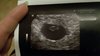

Wspaniale [emoji4]Dziewczyny podnioslyscie mnie na duchu naprawdę , poznajcie w takim razie moje 3mm szczęścia Zobacz załącznik 912011

Super! Ja mam pierwsze usg gdzie nasza fasolka miała 2,6 mm. A później będą takie duże [emoji4]Wspaniale [emoji4]

U mnie jest dokładnie 2.8 mm , a który tydzień miałaś ?Super! Ja mam pierwsze usg gdzie nasza fasolka miała 2,6 mm. A później będą takie duże [emoji4]